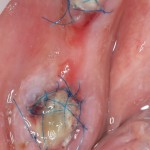

Делаем разрез, скелетируем костную ткань. Вот еще один сюрприз:

Лунка зуба полностью регенерировала! Состояние костной ткани превосходное!

Это еще раз подтверждается, когда мы готовим лунку под имплантат:

Ну и, сам имплантат. Разумеется Friadent XiVE:

Еще раз напомню, что все полированные части импланта любой системы должны находиться выше уровня костной ткани. Как на фотографии.

При таких клинических условиях можно сразу приступить к формированию десны: